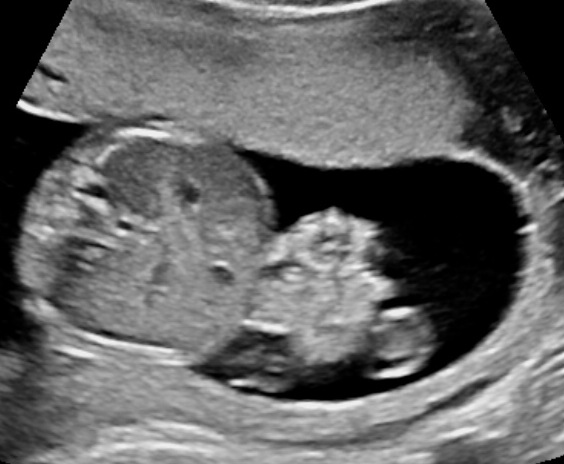

Diagnosing Polyhydramnios

The gestational week does not influence the diagnosis of polyhydramnios. The size of the uterus could be suggesting of this condition, however the diagnosis should be made during ultrasound examination. There are two common ways to estimate the volume of the amniotic fluid:

- Single Deepest Pocket (SDP). A vertical measurement in the deepest amniotic fluid pocket. Values below 2 cm indicate oligohydramnios, values over 8 cm indicate polyhydramnios (8-11: mild, 12-15: moderate, > 16: severe). In multiple gestation, a range of 3–8 cm is defined as normal. Another technique is the

- Amniotic Fluid Index (AFI). This is the sum of vertical measurements of all four quadrants (polyhydramnios usually >24).